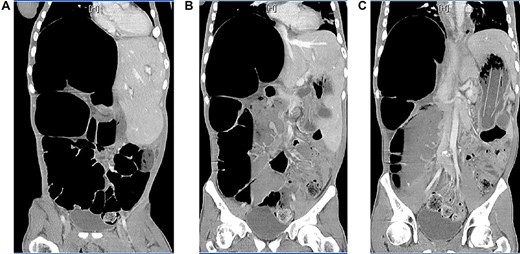

A 36-year-old male presented to the emergency room (ER) for not having a bowel movement, abdominal distension, decreased appetite and increased lethargy for 3 days. Patient is nonverbal, so majority of the history was obtained from his caretaker. He reported a past medical history of severe autism. Vitals were temperature 98.8 F, blood pressure 127/88 mmHg, heart rate 125 beats per minute, respiratory rate 24 breaths per minute and oxygen saturation 94%. On physical examination patient appeared somnolent with a distended abdomen, decreased bowel sounds and mild diffuse tenderness on palpation. Laboratory results were significant for white blood count (WBC) 25.8 U/L, hemoglobin (Hg) 12.3 g/dL, platelet 370 × 103 U/L, blood urea nitrogen (BUN)/creatinine 14/0.5 mg/dL, aspartate aminotransferase (AST) 13 U/L, alanine aminotransferase (ALT) 12 U/L, alkaline phosphatase 121 U/L, lipase 25 U/L and lactic acid 4.64 mmol/L. Computed tomography (CT) scan demonstrated marked distension of the cecum and a colonic loop in the right upper abdomen due to a volvulus possibly in the ascending colon and is unable to visualize the transverse and proximal descending colon and a foreign body within the stomach (Fig 1A–C). Patient was taken for an emergent exploratory laparotomy; however prior to the procedure, he underwent an esophagogastroduodenoscopy (EGD). A foreign body was found in the stomach, but it was too large to be extracted on EGD. Examination of the abdominal cavity intraoperatively revealed a dilated colon (15 cm), a large section of volvulized colon in the right upper quadrant and a segment of volvulus in the distal transverse colon. Patient underwent an extended right hemicolectomy with anastomosis of the terminal ileum to the transverse colon at the level of the splenic flexure. He also underwent a gastrotomy to remove the foreign body, which appeared to be rolled up tar paper. He was started on empiric antibiotic regimen of vancomycin, ciprofloxacin and metronidazole for 2 days. His antibiotics were de-escalated to ceftriaxone and metronidazole and continued for an additional 5 days. Patient had a nasogastric tube placed following the procedure which continued to drain bilious material for 3 days before it was removed. His diet was advanced as tolerated. He was safely discharged to his group home, and no complications were noted at patient’s 2-week follow-up with general surgery.

Axial view of CT of abdomen and pelvis with intravenous contrast (A) & (B), dilated cecum and colonic loop in the right upper quadrant and (C) foreign body within the stomach.